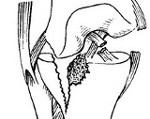

При свежих переломах со значительной компрессией, неправленых и застарелых переломах, а также вторичном оседании мыщелков из-за преждевременной нагрузки на ногу выполняют костнопластическую операцию по Ситенко. Вскрывают сустав, производят остеотомию, приподнимают верхний фрагмент мыщелка так, чтобы его суставная поверхность располагалась на одном уровне и в одной плоскости с поверхностью второго мыщелка, а затем вводят в образовавшуюся щель клин, изготовленный из аутогенной или гетерогенной кости. Фрагменты скрепляют стягивающими шурупами и пластиной.